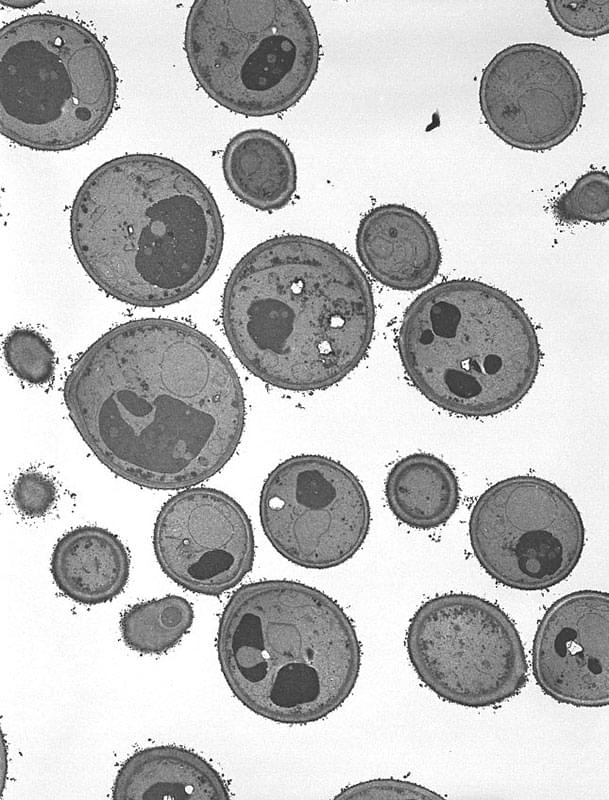

【肝細胞(ブタの肝臓)】

✕7.000 挿入写真 細胞膜(✕100,000)

- 肝臓は脂質、蛋白の合成、薬剤などの代謝と除去、エネルギーの貯蔵など多くの機能を有している。これを構成しているのがほとんど肝細胞であり、その他毛細胆管(BC)や血管(HS)があり血管の中には血液細胞(EC、Kf)がみられる。

- 肝細胞は細胞膜(CM)に囲まれ1つの細胞核(N)を持っている。細胞質には蛋白質を合成する小胞体(rER)、細胞エネルギーを作り出すミトコンドリア(M)、糖を貯蔵するグリコーゲン(Gl)がある。挿入写真は隣り合った細胞の細胞膜の拡大で、それぞれの細胞膜は幅約7nmの2重構造であることが判る。

- 肝細胞は一般的な細胞の構造と機能を解説する時に常に引き合いに出されるくらい、典型的な細胞小器官を持っている。